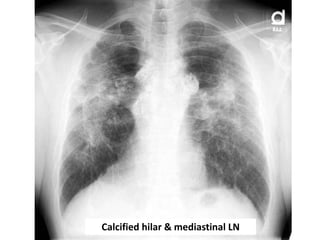

DD of calcified hilar or mediastinal LN

• Silicosis

• Sarcoidosis.

• TB.

• Treated lymphoma.

Calcified hilar & mediastinal LN